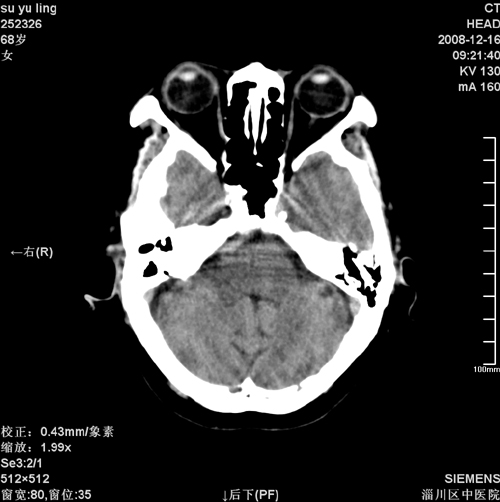

女,68岁,左侧肢体活动不利。

1)考虑镰旁脑膜瘤钙化。2)小脑萎缩。